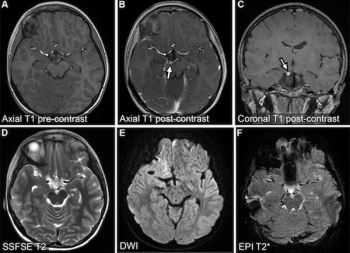

FIRMM-pix, a brain magnetic resonance imaging (MRI) software module recently launched at the International Society for Magnetic Resonance in Medicine (ISMRM) conference, reportedly employs visual biofeedback and gamification that coaches patients to stay still during brain MRI exams.